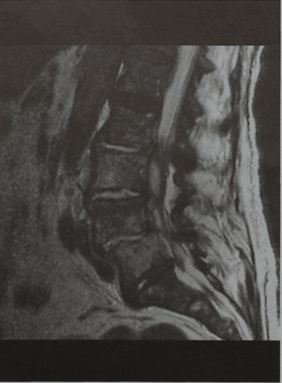

Рецидивирующие боли с повышением уровня маркеров воспаления (сепсис) после спондилодисцита. МРТ поясничного отдела позвоночника (сагиттальная проекция, Т2-взвешенное изображение). Двояковыпуклое эпидуральное объемное образование на уровне позвонка LIII. Образование дает равномерный сигнал повышенной интенсивности, оно отграничено от спинного мозга капсулой, дающей слабый сигнал. Повышена интенсивность сигнала от межпозвоночных дисков на уровне от LII- LIII до LIV -LV

МРТ позвонка LIII (горизонтальная проекция, Т2-взвешенное изображение). Абсцесс распространяется через левое межпозвоночное отверстие в большую поясничную мышцу слева.